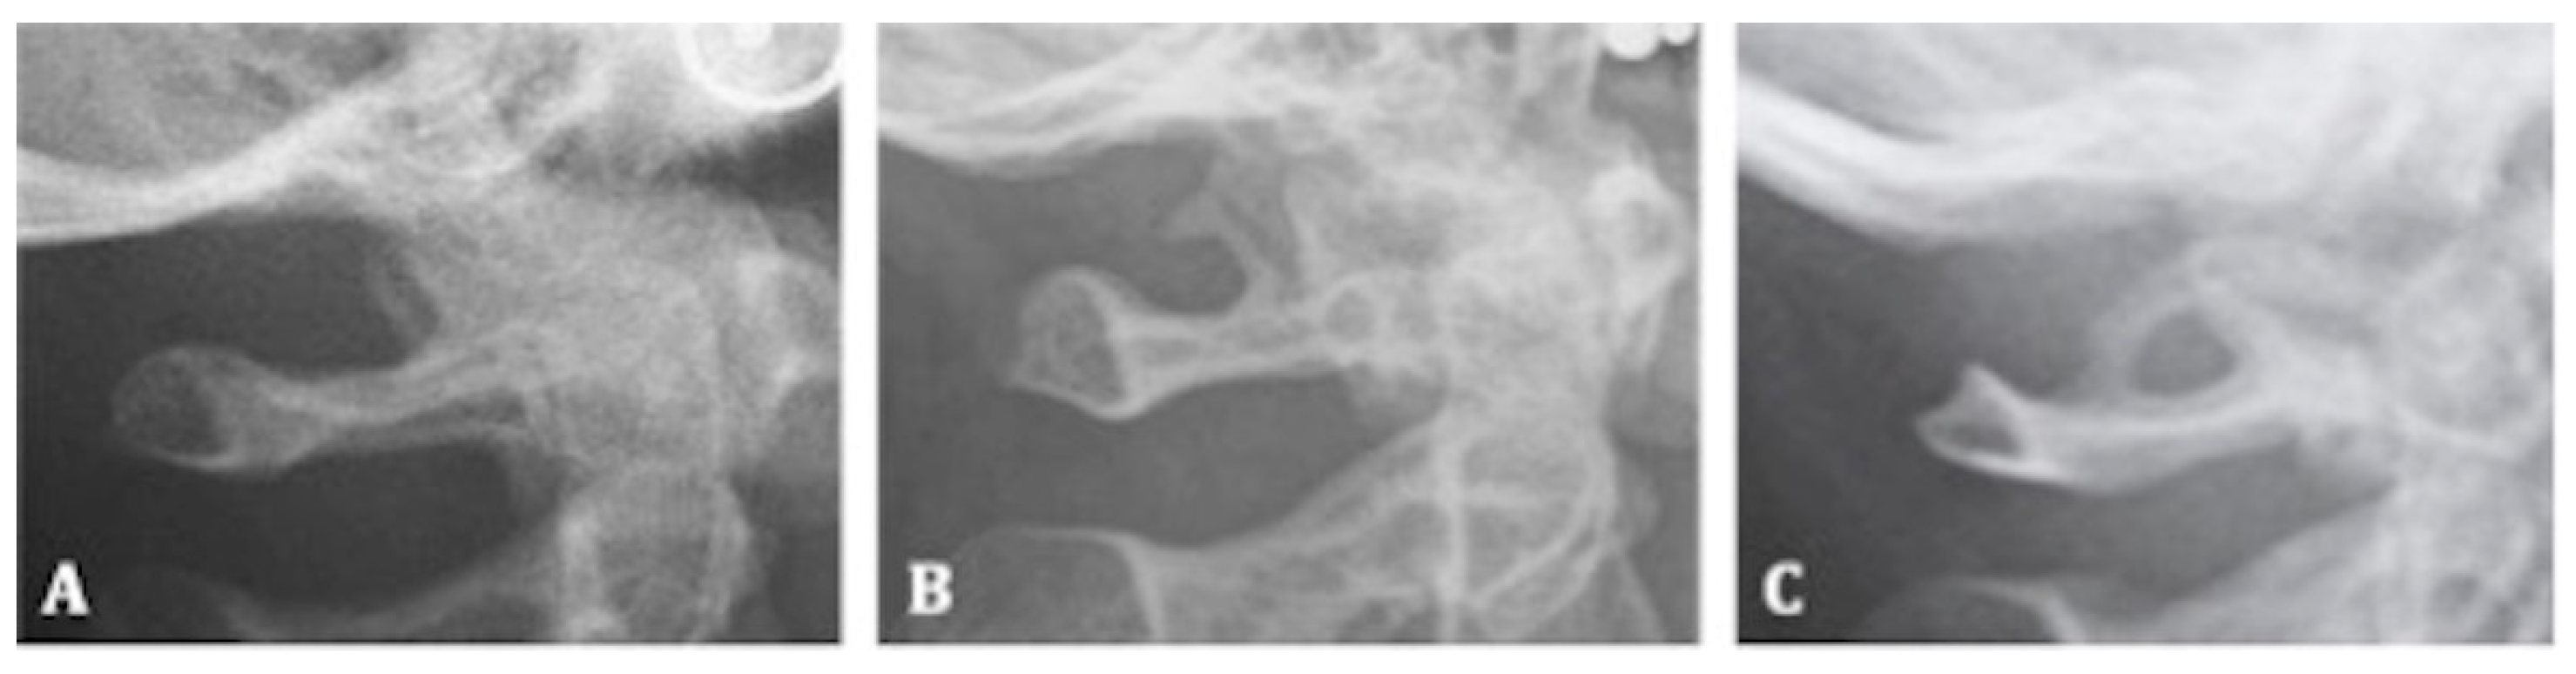

2.5.4. Ponticulus Posticus

- -

- Class I: absence of calcification;

- Class II: incomplete or partial calcification;

- Class III: complete calcification.